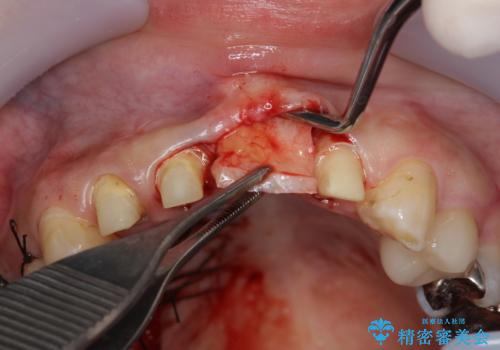

左側の前歯には他院で埋入されたポジションの悪いインプラント補綴により歯冠長の長いクラウンが装着されており、感染による排膿も認められこのまま審美性を改善するのは難しい状態です。

不良インプラントを除去し最終的にブリッジによる補綴で審美性の改善を行うこと、その準備として骨の造成・歯肉の移植による歯の欠損部顎堤のボリュームを維持・増大を計画します。

感染したインプラントからは排膿が間欠的に認められ、掻爬・除去が検討されうるような状況でした。

より審美的な改善を強く求められたため、インプラントを除去し可及的に欠損部顎堤を増大したのちブリッジによる審美改善を行いました。